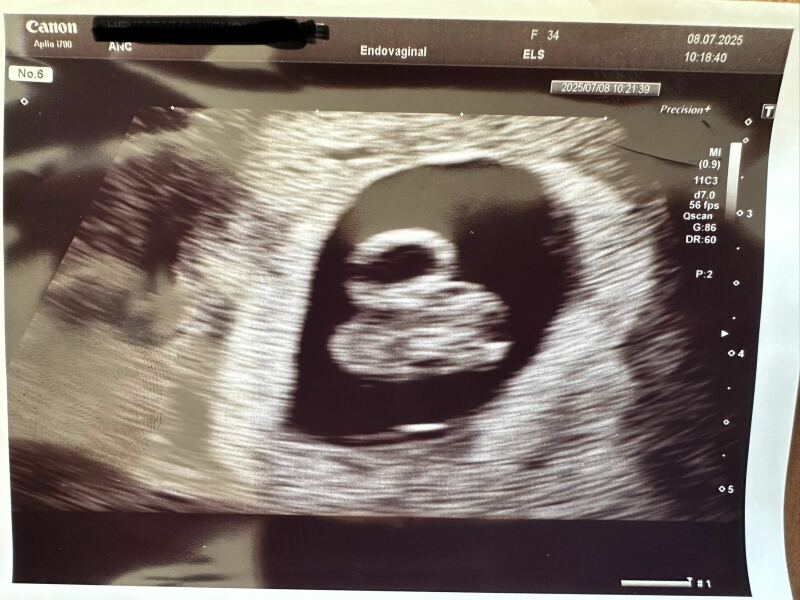

JLucyNick · 08/07/2025 19:25

@DCmum95 Aw bless you. Great news about scan. I’m exactly the same. Bag of nerves all the time. I had my second NHS scan this morning. All good and measuring 7w4d. Iv got my booking appointment on Sunday. Here’s my bean x

Line progress

DCmum95 · 08/07/2025 20:46

That’s amazing! Beautiful scan. I keep saying to my husband how many scans are too many! They’re just so expensive. Feel like I need one every week, even though I know they won’t make anything better but just to ease the nerves. That’s great about your booming appt, I haven’t been contacted about mine yet after self referring, will chase them tomorrow